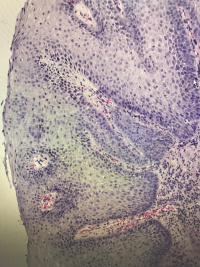

食道粘膜

腹痛,距门齿33cm处食管壁见0.4✖️0.5cm隆起

灰白组织一粒,直径0.1

鳞状上皮乳头状瘤性息肉,局部鳞状上皮轻度异型增生。

鳞状上皮下是幽门腺,胃粘膜异位

贲门部就是幽门腺

鳞上皮乳头上移,副基底层增生